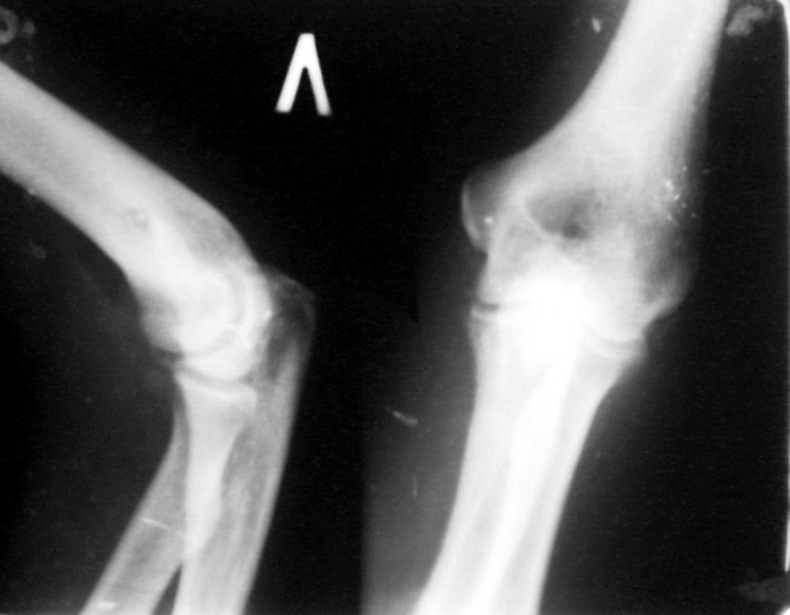

Поступил пациент, 47 лет. травма 15 сентября - вывих предплечья,

репозиция. Фиксация 1 месяц. До настоящего времени не обращался. Вот

рентенограммы на 2-й и 3-й месяцы после травмы. Неврологии нет. Имеется

контрактура локтевого сустава (сгибиние 90, разгибание 120). На снимках

что-то похожее на гетеротопические оссификаты, такое впечатление. Как

лучше восстановить функцию, возможно ли применить редрессацию? Все-таки

локтевой сустав "капризный".